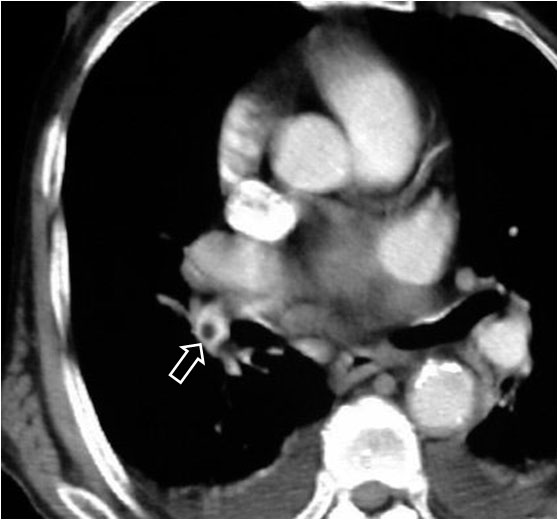

SIGNO DEL ANILLO

Signo de tromboembolismo pulmonar (TEP) en el angioTC con contraste intravenoso. El anillo (flecha) corresponde al contraste que rodea a un trombo central en un vaso cortado transversalmente. Vemos este signo en la arteria lobar inferior derecha. El signo del anillo se ve en el TEP agudo, ya que el trombo ocupa una posición central en el vaso. En el TEP crónico el trombo se hace marginal.

SIGNO DEL RAÍL O DE LAS VÍAS DEL TRANVÍA

Signo de tromboembolismo pulmonar en el angioTC con contraste intravenoso. El trombo aparece como un defecto de repleción intraluminal (arteria pulmonar) rodeado, al menos parcialmente, por un halo delgado de contraste. Este hallazgo tiene el mismo significado que el signo del anillo. La imagen depende de si el vaso es cortado transversalmente (anillo) o longitudinalmente (raíl).